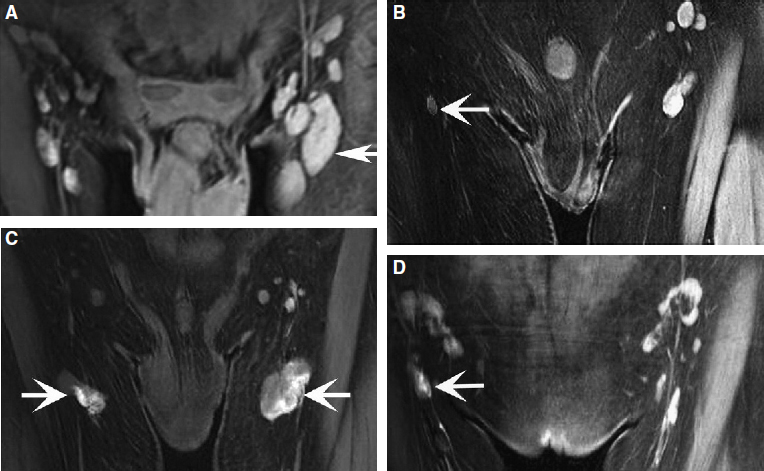

In recent years, medical imaging of the lymphatic system has advanced rapidly. The diagnostic value of new technologies, such as magnetic resonance lymphangiography (MRL), for evaluating the lymphatic system and the stage of disease has increased exponentially. 13 , 14 High-resolution imaging and real-time observation of the structures and functional anomalies of the lymphatics and lymph nodes can help surgeons make a more precise diagnosis (Figs. 45-2 and 45-3) and accurately identify the type or subtypes of lymphatic pathologies (Fig. 45-4).

Based on the more comprehensive evaluation of a patient’s lymphatic system that is made possible by MRL, appropriate surgery can then be selected, treatment can be much better individualized, and an improved curative effect can be expected. By the same token, the previous lack of high-resolution imaging also meant a lack of reliable tests to objectively evaluate the patency of lympha ticovenous anastomoses or lymphatic regeneration after free lymph node transfers. Sometimes it was difficult to determine whether the decrease in patient bulk was from restoration of the lympha tic circulation or from bandaging and bed rest in the hospital after surgery. The three-dimensional dynamic MRL may help provide an objective measure of clinical outcome and prognosis.